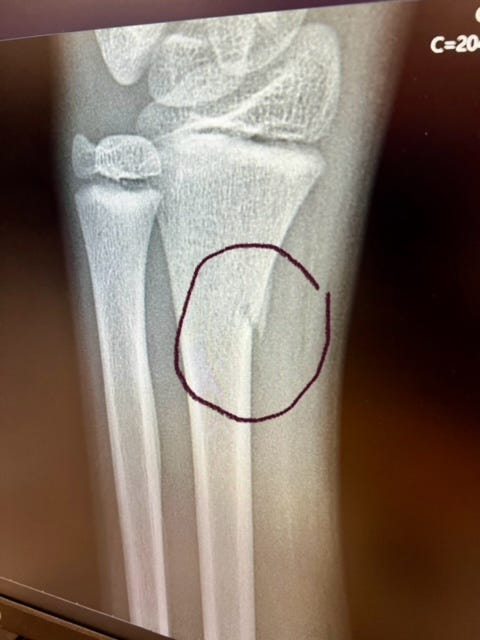

His right side got torn up. But his left wrist was worse.

He “only” broke his wrist was our reaction. This next picture illustrates why.